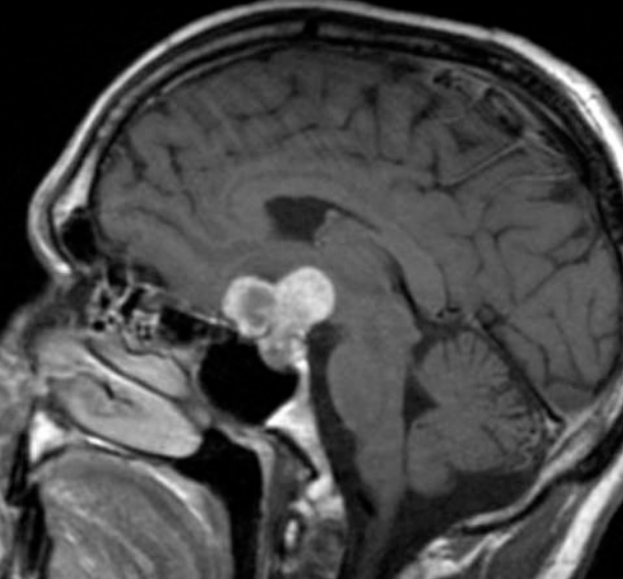

颅咽管瘤是比较常见的良性肿瘤,占颅内肿瘤的2%~5%,在儿童中尤为常见,位居儿童颅内肿瘤的2位,约占儿童颅内肿瘤的5.6%~15%,占儿童鞍区肿瘤的54%。颅咽管瘤主要有2个发病高峰期:5~15岁的儿童以及40岁左右的成人。通常颅咽管瘤的治疗以手术为主,手术后的康复期也是重要的。那么,颅咽管瘤术后多久恢复痊愈?

颅咽管瘤术后多久恢复痊愈?颅咽管瘤虽然治疗方法有手术、放疗、化疗等多种方式,但是手术是治疗颅咽管瘤的主要手段。颅咽管瘤虽然是良性肿瘤,但位置深在,毗邻重要神经血管结构,部分患者手术难度较高。颅咽管瘤的手术治疗需要在充分保护垂体-下丘脑功能及视路结构的前提下地追求全切除方能治愈。对于严重侵犯下丘脑结构的颅咽管瘤,手术中对三脑室壁结构与肿瘤间形态学关系的充分辨识至关重要,可较大限度地提高其全切除率。如果术后肿瘤残留,在充分告知患者放疗并发症(导致内分泌水平下降、导致再次手术困难等)的前提下,放疗是可能的选择。因为治疗策略与手术水平的不一,因此,不同报道的复发率、生存率、垂体-下丘脑功能、生存质量等差别较大。